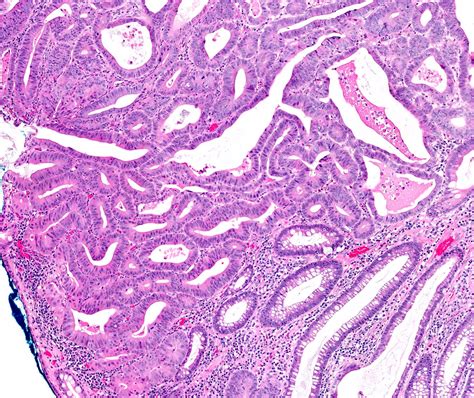

High Grade Dysplasia refers to abnormal changes in the cells lining the esophagus. These changes are more severe than those seen in low-grade dysplasia and indicate a higher risk of developing esophageal cancer. Barrett's esophagus, a condition where the normal cells lining the esophagus are replaced by cells similar to those found in the intestine, is a common precursor to high-grade dysplasia.

• Biopsy: During an endoscopy, tissue samples are taken from the esophagus and examined under a microscope to detect abnormal cells.

No Dysplasia Normal cells with no abnormal changes. Low

Low-Grade Dysplasia Mild abnormal changes in the cells. Moderate